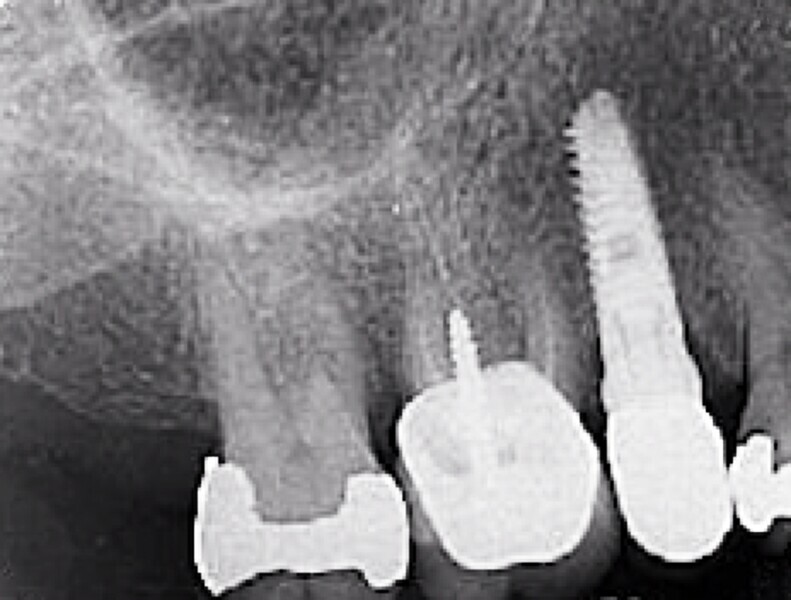

Fig. 1 : Radiographie avant l’extraction (première phase).

Fig. 2 : Radiographie avant l’extraction (première phase).

La première phase du traitement implantaire a consisté à extraire la dent et à préserver l’alvéole au moyen d’une allogreffe et d’une membrane de collagène. Six mois après, l’os régénéré a permis de procéder à la seconde phase du traitement comportant la pose d’un implant deux pièces en céramique (Figs. 1–11).